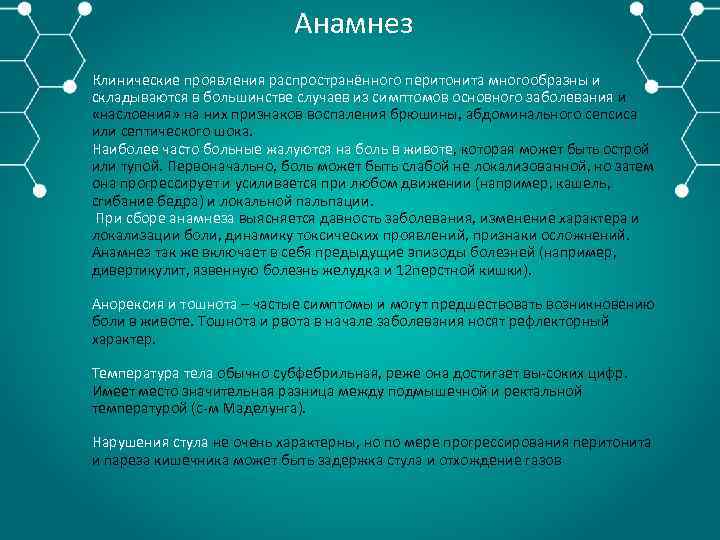

Анамнез Клинические проявления распространённого перитонита многообразны и складываются в большинстве случаев из симптомов основного заболевания и «наслоения» на них признаков воспаления брюшины, абдоминального сепсиса или септического шока. Наиболее часто больные жалуются на боль в животе, которая может быть острой или тупой. Первоначально, боль может быть слабой не локализованной, но затем она прогрессирует и усиливается при любом движении (например, кашель, сгибание бедра) и локальной пальпации. При сборе анамнеза выясняется давность заболевания, изменение характера и локализации боли, динамику токсических проявлений, признаки осложнений. Анамнез так же включает в себя предыдущие эпизоды болезней (например, дивертикулит, язвенную болезнь желудка и 12 перстной кишки). Анорексия и тошнота – частые симптомы и могут предшествовать возникновению боли в животе. Тошнота и рвота в начале заболевания носят рефлекторный характер. Температура тела обычно субфебрильная, реже она достигает вы соких цифр. Имеет место значительная разница между подмышечной и ректальной температурой (с м Маделунга). Нарушения стула не очень характерны, но по мере прогрессирования перитонита и пареза кишечника может быть задержка стула и отхождение газов